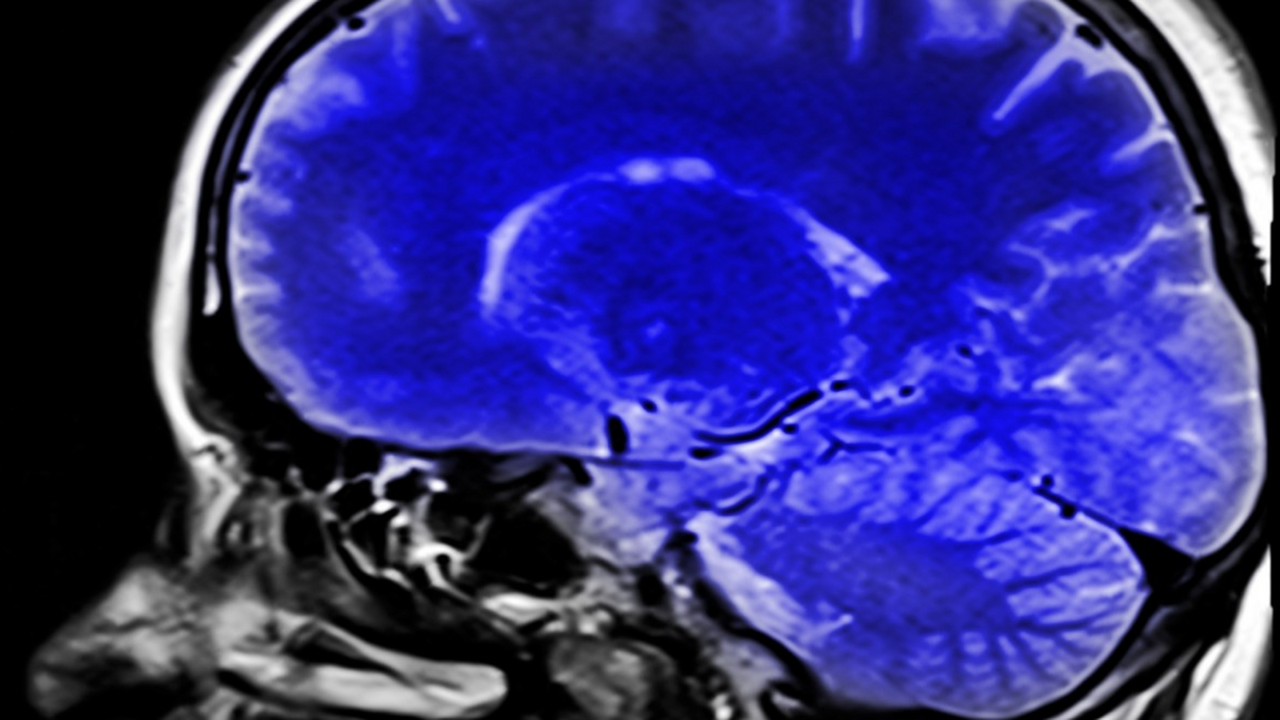

Исследователи обнаружили новый механизм, который помогает мозгу избавляться от токсичных белков. Речь идет о клетках, известных как танциты, которые участвуют в выведении белка тау — одного из факторов развития болезни Альцгеймера.

В ходе экспериментов ученые установили, что эти клетки способны транспортировать молекулы токсичного белка из тканей мозга в спинномозговую жидкость. Таким образом организм получает возможность выводить вредные вещества.

Накопление белка тау считается одним из ключевых процессов, связанных с нейродегенеративными заболеваниями. Его избыток приводит к разрушению нейронных связей и ухудшению памяти.

По мнению специалистов, обнаруженный механизм может стать основой для разработки новых методов лечения деменции и других заболеваний нервной системы. Если ученым удастся усилить естественный процесс очищения мозга, это может замедлить развитие болезни Альцгеймера.